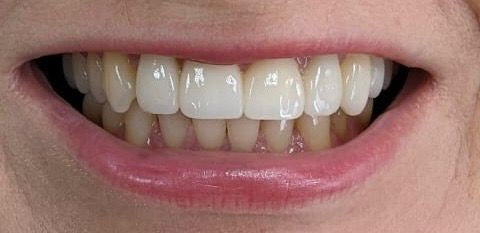

Установка коронки из диоксида циркония

Диоксидциркониевые конструкции цифрового моделирования на зубы верхней челюсти. Состояние после снятия старых коронок и фото в день фиксации.

Доктор: Тытарь Денис Владимирович

Установка коронки из диоксида циркония

Диоксидциркониевые конструкции цифрового моделирования на зубы верхней челюсти. Состояние после снятия старых коронок и фото в день фиксации.

Доктор: Тытарь Денис Владимирович